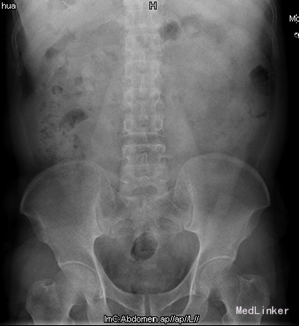

患者,男,55岁8月,因“反复腰背部胀痛6+月”入院。6+月前,患者无明显诱因出现腰背部间歇性胀痛,无发热、恶心、呕吐,无尿频、尿急、尿痛,无肉眼血尿等症状,于当地医院查彩超示“双肾结石”行“左肾结石体外震波碎石”,因“右肾囊肿”而未处理“右肾结石”,术后患者恢复良好,无发热、腹胀、腹痛等不适。此后患者反复出现右侧腰背部不适,未予特殊处理。10+天前,患者自觉右侧腰背部胀痛加重,呈持续性,不伴发热,无肉眼血尿,无尿频、尿急、尿痛等症状,遂于我院门诊行CT示“右肾柱形状结石,右肾积水,右肾萎缩,右侧输尿管下段膀胱入口处结石影”。现患者为进一步诊治入院。

查体:腹部外形正常,全腹柔软,无压痛及反跳痛,腹部未触及包块,肾脏未触及;右肾区叩痛明显,左肾区无叩痛;双侧输尿管压痛点无压痛。 CT:右肾柱形状结石,右肾积水,右肾萎缩,右侧输尿管下段膀胱入口处结石影; 核素肾显像:左肾GFR:30.2ml/min,右肾19.4ml/min。

诊断:1、右肾结石 2、右侧输尿管开口囊肿 3、右侧输尿管下段结石 4、右肾囊肿 5、尿路感染 行右肾碎石术,术中见:右侧输尿管开口处一囊肿,约1.0cm×0.8cm,压迫右侧输尿管开口,随输尿管口喷尿时呈隆起行改变,囊肿内发现一大小约0.5×0.2cm大小结石,右肾盂大量沙粒样结石。